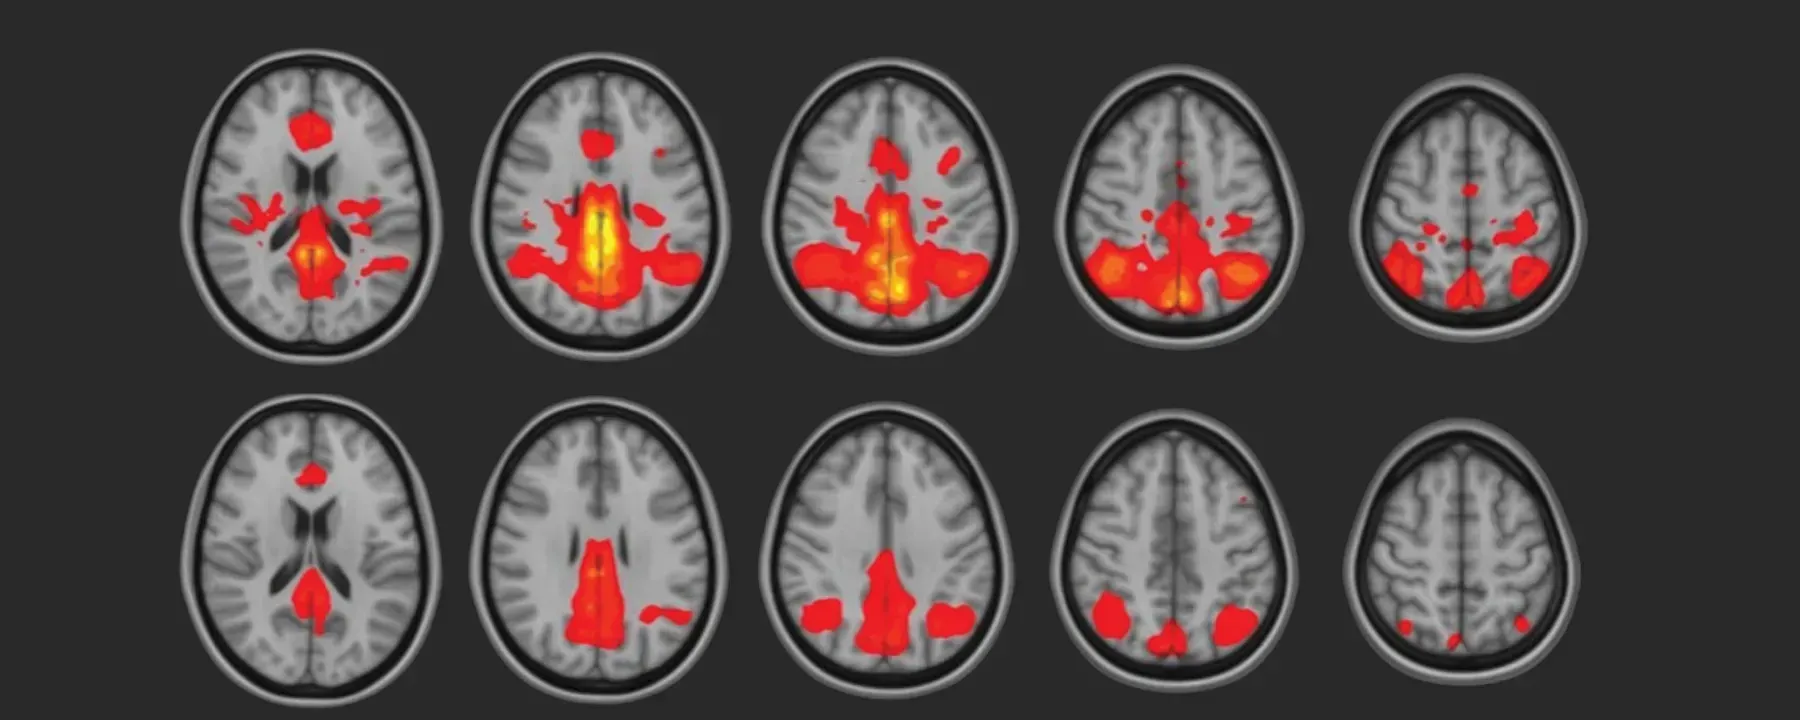

Lids for Kids is a start up non-profit to bring awareness to our youth community about concussions and how to help prevent head injuries.

I’ve always been fascinated by the brain, and that interest grew into a focused study of concussions and CTE, especially in athletes whose careers I followed closely. What began as an AP Research project evolved into a broader commitment to understanding and improving helmet design, materials, and athlete safety.